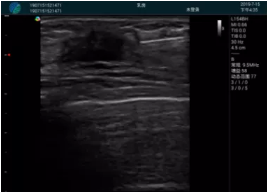

腺體內部清晰顯示一低回聲塊影,形態(tài)不規則,邊界模糊,邊緣呈毛刺狀,內部見(jiàn)砂礫樣鈣化

M20引導下穿刺活檢術(shù)

M20引導下平面內穿刺取出的腫塊組織